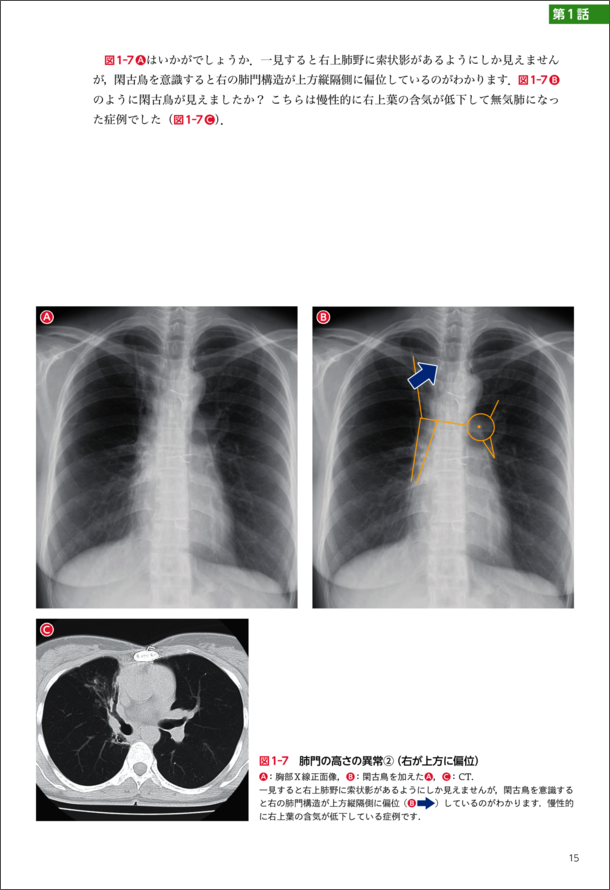

『第1話 肺門編「閑古鳥を探せ!」』より抜粋